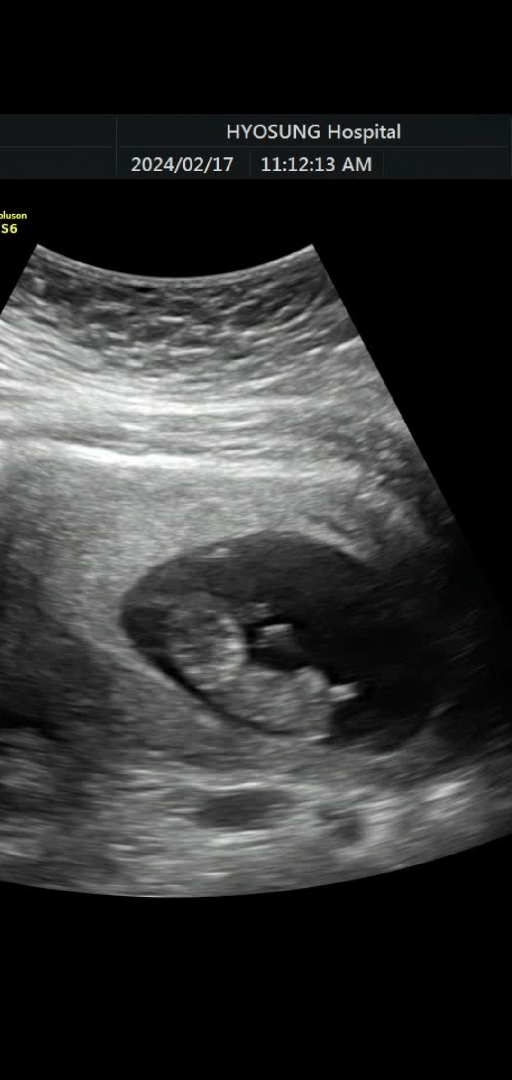

10주 2일 벌써 손가락을 빨아요 😆

오늘 촘파 보고왔는데 선생님이 손가락을 입에넣었다 하면서 빨고 있네요~하는데 너무 귀엽네요❤️ 😍